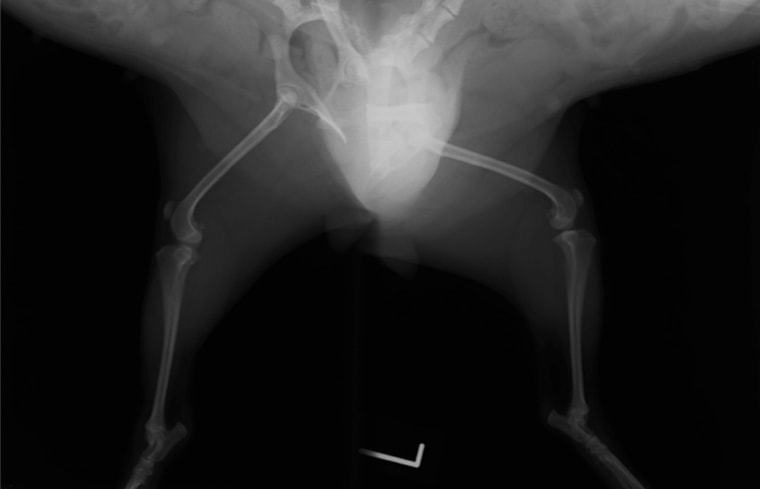

■ 症例20 ポメラニアン 8ヶ月 1.8kg

左右膝蓋骨脱臼 グレードⅢ

2ヶ月前から間欠的跛行が認められ、両膝の膝蓋骨脱臼整復術を行った。

手技は縫工筋及び内側広筋の解放、脛骨粗面の外側転位、滑車ブロック形造溝術、内外側関節包の縫縮を選択し実施した。

右側の膝蓋骨脱臼は上記手技で整復されたものの、左側はそれのみでは膝蓋骨が浮く様子が認められた。その為、PDS縫合糸にて膝蓋靱帯を1糸のみ縫合し、靱帯の縫縮を行った。

膝蓋骨脱臼は膝関節における膝蓋骨の内外側の脱臼と定義されるが、時として単純な内外の脱臼ではなく、膝蓋骨が大きく前方に浮き上がるように脱臼する場合がある。特にトイプードルやポメラニアンといった犬種に多く認められる。

内側脱臼に加えて前方への浮き上がりを矯正する為に、従来より脛骨粗面転移により膝蓋靭帯を外方と下方に引っ張り、固定する方法を選択する。膝蓋骨の前方への浮き上がりが軽度の場合は、従来法ではなく関節包の縫縮で対応していた。しかし、一部の症例で膝蓋骨の動きが悪くなり伸展機構が円滑に機能せずロボット様歩行になるケースがあった。

その為、膝蓋靭帯自体を縫縮する方法を採用した。この方法により、膝関節の伸展機構を妨げず膝蓋骨の軽度の浮きを矯正することが可能となった。

本症例の経過は良好である